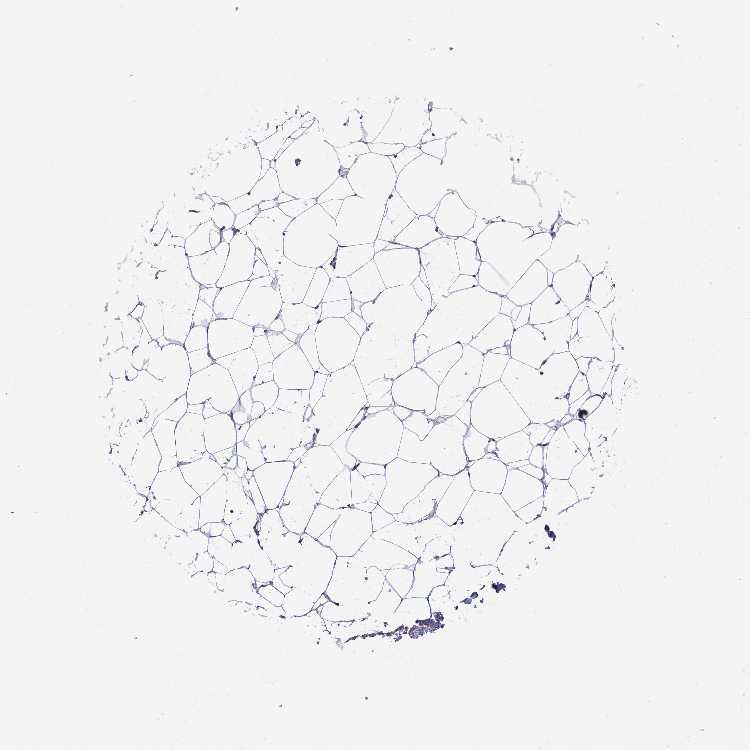

BREAST - Antibody stainingi

Antibody staining in the annotated cell types in the current human tissue is reported as not detected, low, medium, or high, based on conventional immunohistochemistry profiling in selected tissues. This score is based on the combination of the staining intensity and fraction of stained cells.

Each image is clickable and will lead to virtual microscopy that enables deeper exploration of all samples and also displays staining intensity scores, fraction scores and subcellular localization as well as patient and tissue information for each sample.

Antibody HPA000289Antibody CAB019435Antibody CAB073410

Adipocytes Not detectedMediumLow

Glandular cells LowMediumMedium

Myoepithelial cells Not detectedMediumMedium